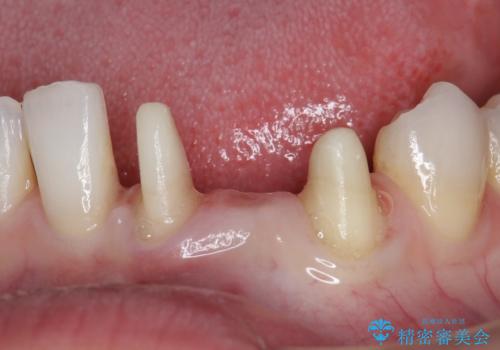

- 他院にて矯正治療を行ったが、左下の前歯の見た目が気になるのでセラミックで治したいといらっしゃった方の症例です。

左下123番のブリッジになるが、左下1番と3番の歯軸が合っておらず神経治療が必要になる可能性があるため部分矯正を提案したところ、希望されなかったため、そのままの歯軸でオールセラミッククラウンによる補綴を行いました。